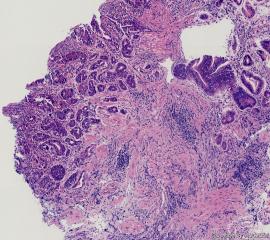

贲门息肉,低级别上皮内瘤变?

贲门息肉

灰白灰褐色针头大组织一块。胃镜示:贲门见一黄豆大粘膜增生,表面稍粗糙。

贲门息肉,达不到上皮内瘤变

符合贲门息肉。

符合管状腺瘤,低级别上皮内病变。